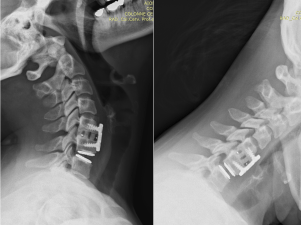

Hybrid stabilization with fusion and cervical disc replacements